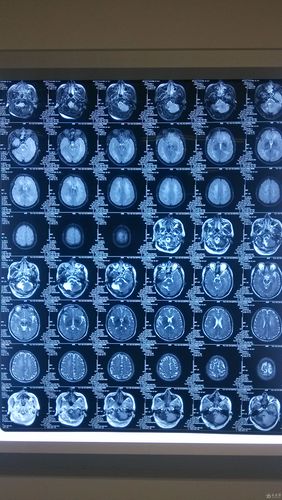

“多发”的含义: “多发”意味着在头颅CT或MRI(磁共振)上发现了两个或以上的梗死灶,这些梗塞灶可能位于大脑的不同区域,说明脑血管的阻塞不是一次性的,而是反复发生的。